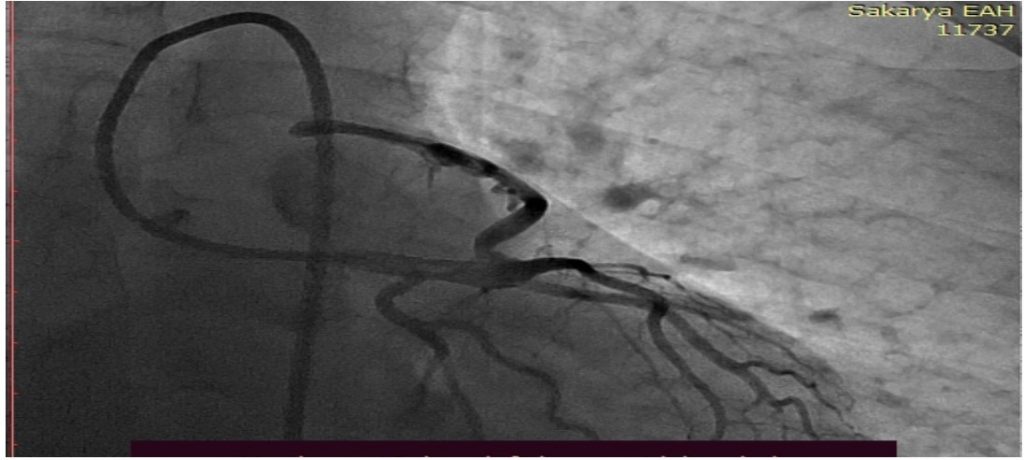

Sakarya Üniversitesi (SAÜ) Tıp Fakültesi Öğretim Üyeleri Prof. Dr. Ramazan Aydemir, Dr. Öğretim Üyesi Yusuf Can ve Arş. Gör. Dr. Ahmet Can Çakmak, kalp damar hastalığı tedavisinde dünyada ilk kez uygulanan bir yöntem geliştirdi.

Doğuştan kalp damar hastalığına sahip olan 42 yaşındaki bir erkek hastaya uygulanan yönteminin en büyük özelliği, hem Koroner Arter Fistülünü tam olarak kapatırken hem de sistemin düşme veya hastanın damarında kaybedilme riskini ortadan kaldırıyor.

Söz konusu yeni teknikte bir koroner anjiyoplasti balonunun bir koroner stent üzerine ameliyat dikiş ipliği ile sabitlenerek, kapatılması planlanan hedef damara ulaşılmakta, stent şişirilmesi ile damar tıkanılıyor.

Doğuştan kalp damar hastalığına sahip olan 42 yaşındaki bir erkek hasta, dünyada ilk kez uygulanan yeni bir teknikle tedavi edildi. Başarılı operasyonun 3 ay önce Düzce’den sevk edilen bir hastaya uygulanmıştı.

Hastanın şikâyetlerinin kalp damarı ile akciğer damarı arasında doğuştan gelen ve kan sızıntısına yol açan fazladan bir damara bağlı olduğu teşhis edilmişti. Hastalığın bu güne kadar yapılan tedavilerinin yüksek maliyetli ve başarısız olduğunu bilen SAÜ Tıp Fakültesi üyeleri, yeni operasyon tekniği geliştirme kararı aldı. Söz konusu operasyon tekniğini doktor ekibi, önce testler yaparak, hastanın zarar görmeksizin bu yeni tedavi ile eksiksiz tedavi edilebileceğine kanaat getirdikten sonra, hastayı ameliyata aldı.

Prof. Dr. Ramazan Aydemir, Dr. Öğretim Üyesi Yusuf Can ve Dr. Ahmet Can Çakmak’ın birlikte yaptıkları ameliyatın ardından 3 ay geçmesine rağmen hastanın herhangi bir şikâyeti bulunmuyor.